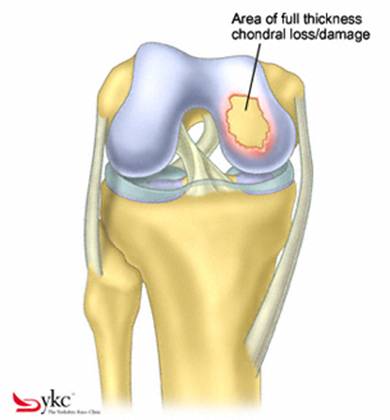

Chirurgul trebuie sa fie foarte atent atunci cand examineaza posteriorul condililor femurali. Daca se semnaleaza orice vatamare/rana/deteriorare pe suprafetele articulare, trebuie sa se cerceteze atent calitatea cartilajului. Orice flapsuri instabile sunt inlaturate prin folosirea unui aparat de ras electric artroscopic sau curette. Apoi, un curette este folosit pentru a debrida stratul de cartilagiu calcifiat de la baza in toata grosimea defectului. Acest pas se bazeaza pe activitatea lui Frisbi, care a demonstrat vindecarea suprafetei articulare superioare la un cal, cand stratul cartilagiului calcifiat este indepartat. Cand indepartam stratul cartilajului calcifiat, in general nu se foloseste un aparat de ras. Cu un aparat de ras este dificil de controlat cantitatea de os eliminat, si este posibil ca osul subcondral sa fie afectat.

Fig.21. Diagrama unei leziuni cartilaginoase.